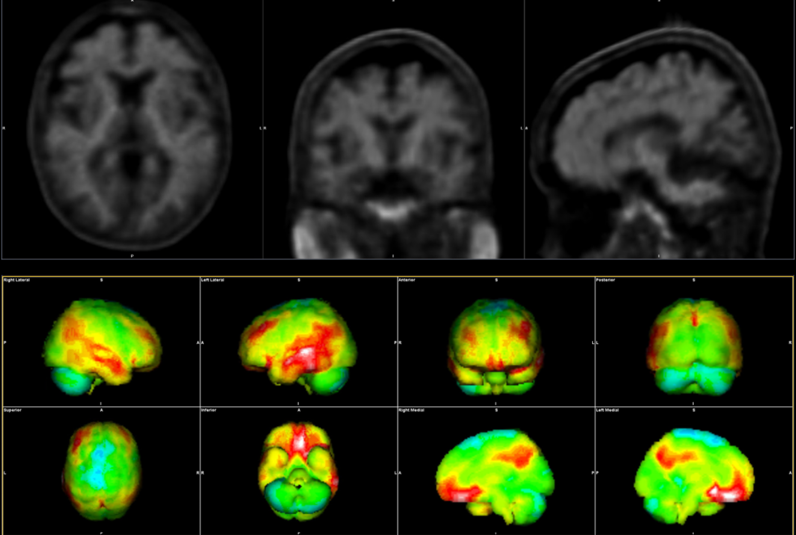

King’s College London is the first in the UK to benefit from two Biograph Vision Quadra whole-body PET-CT systems, representing a major leap forward in medical imaging